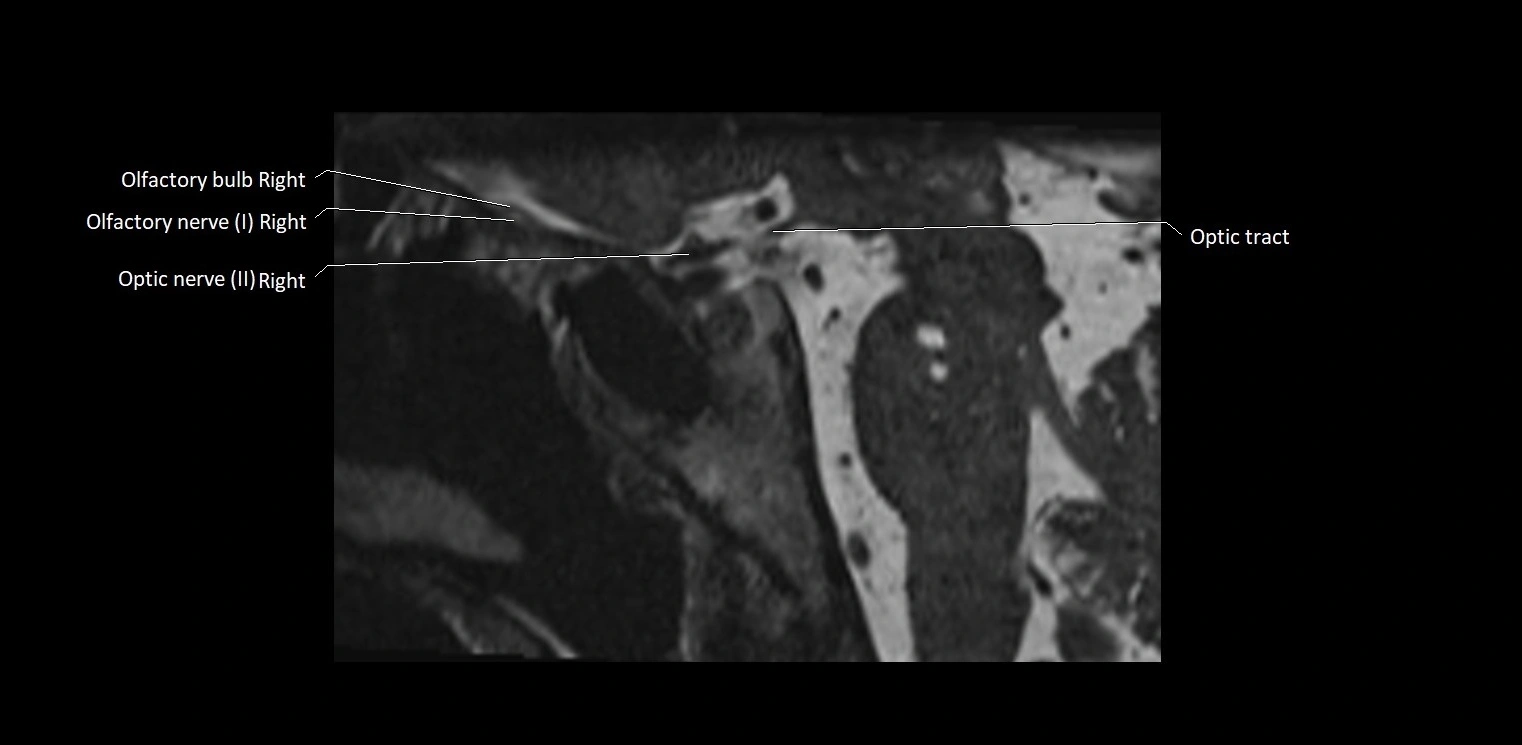

MRI Appearance

• The abducens nerve is a small, thin, linear structure

• Best visualized on high-resolution T2-weighted 3D MRI sequences (e.g., FIESTA or CISS)

• Seen as a hypointense (dark) line running from the brainstem at the pontomedullary junction, traversing the prepontine cistern, and entering Dorello’s canal under the petrosphenoidal ligament, then into the cavernous sinus, and finally the orbit

• May be challenging to visualize in standard MRI due to its small size

• Pathology may be inferred by absence, displacement, or enhancement of the nerve